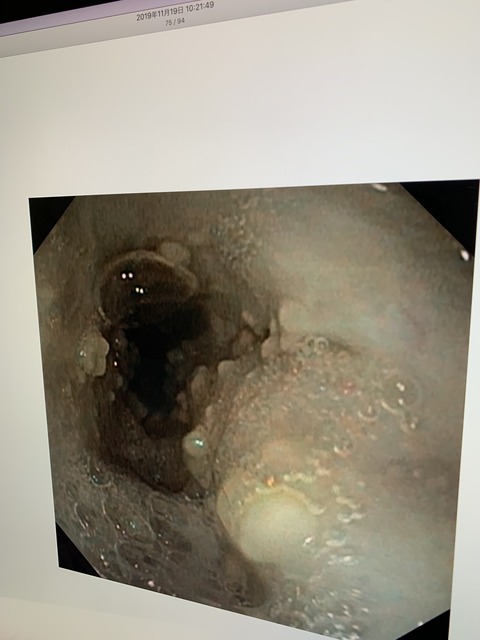

でも、微熱と言うか、40度ぐらいの熱が続くカカオは、若干、腹水もみられ、

最悪な事にFIPの診断が下されてしまいました。。。